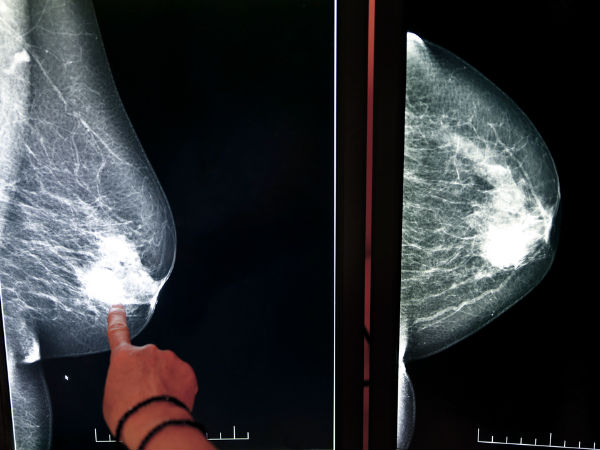

மார்பக புற்று நோயை தடுக்கும் ஒரு அற்புத உணவு இதுதாங்க!! ஆராய்ச்சியாளர்களெ சொல்லிட்டாங்க!!

புதிய ஆராய்ச்சி படி பார்த்தால் சோயா உணவில் உள்ள கூட்டுப் பொருட்கள் மார்பக புற்றுநோயை ஒடுக்கும் தன்மை கொண்டு உள்ளது என்பது கண்டுபிடிக்கப்பட்டுள்ளது. அதைப் பற்றிய ஒரு தொகுப்பு

மார்பக புற்று நோய் எல்லாரையும் அச்சுறுத்தும் ஒரு வகை கேன்சர் நோயாகும். இதனால் ஒவ்வொரு வருடமும் மில்லியன் கணக்கிலான பெண்கள் பாதிப்படைகின்றனர். இதில் ஒரு சில பேர்கள் மட்டுமே சரியான நேரத்தில் கண்டுபிடித்து சரியான சிகச்சை மேற்கொண்டு வெற்றி கரமாக அதிலிருந்து மீள்கின்றனர்.